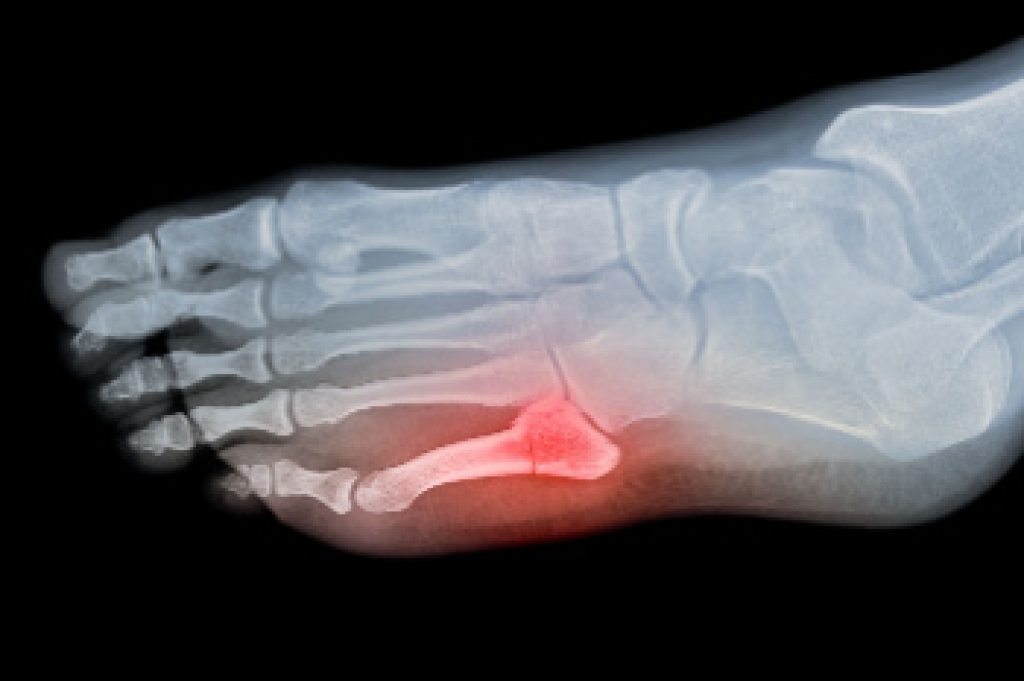

- Removing foot deformities like bunions and bone spurs

- Severe arthritis that has caused bone issues

- Bunionectomy for painful bunions